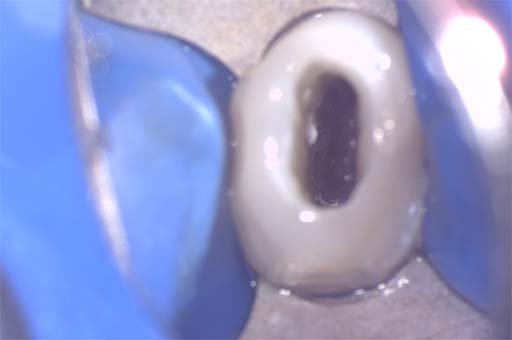

治療画像

APICO後